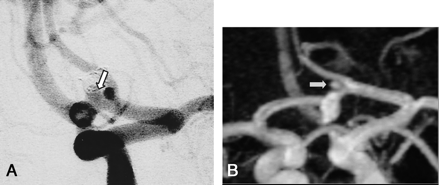

A, DSA of the left internal carotid artery performed at 12 months after treatment of a 3-mm aneurysm of the anterior communicating (arrow). The frontal head view shows no residual neck or aneurysm (class 1).

B, Contrast-enhanced MR angiograph with MIP reconstruction in the frontal plane shows a hypersignal (arrow) at the site of the anterior communicating artery misinterpreted as a residual neck (class 2).